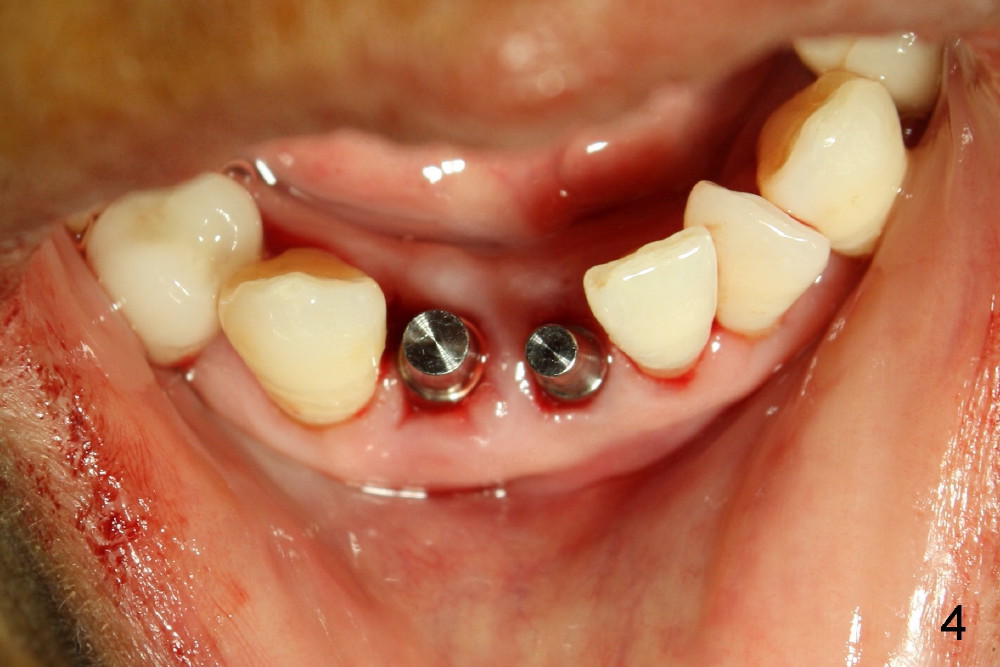

A 60-year-old lady wants to remove 2 mobile lower right incisors (Fig.1,2; with infection at the lateral (>)). Immediate 1-piece implants are placed (Fig.3,4): 3x17 mm at the central, 3.5x17 mm at the lateral. Insertion torque is > 60 Ncm for the implants. No bone graft is placed. After prep (Fig.5), two separate provisionals are fabricated (Fig.6). The one at the lateral incisor looks bulky at the cervix, because of the oversized implant for the site (over-engineering). Use of smaller implant (3.0 (instead of 3.5), 2.5 (instead of 3.0) or 2.0 mm) may solve the problem. Seven days postop, the infection resolves (Fig.7 >) with normal-looking papilla (*).